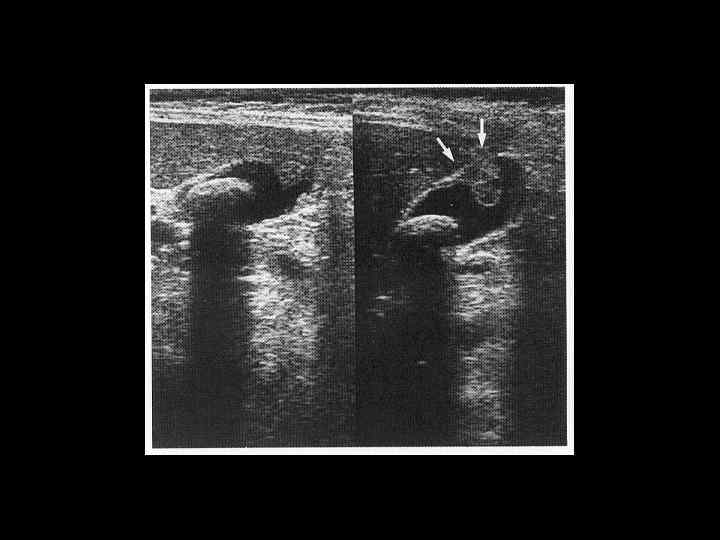

АКТУАЛЬНЫЕ ВОПРОСЫ РЕНТГЕНОЛОГИИ ЛУЧЕВАЯ ДИАГНОСТИКА ЗАБОЛЕВАНИЙ ЖЕЛЧЕВЫДЕЛИТЕЛЬНОЙ СИСТЕМЫ Острый и хронический холецистит УЗ семиотика